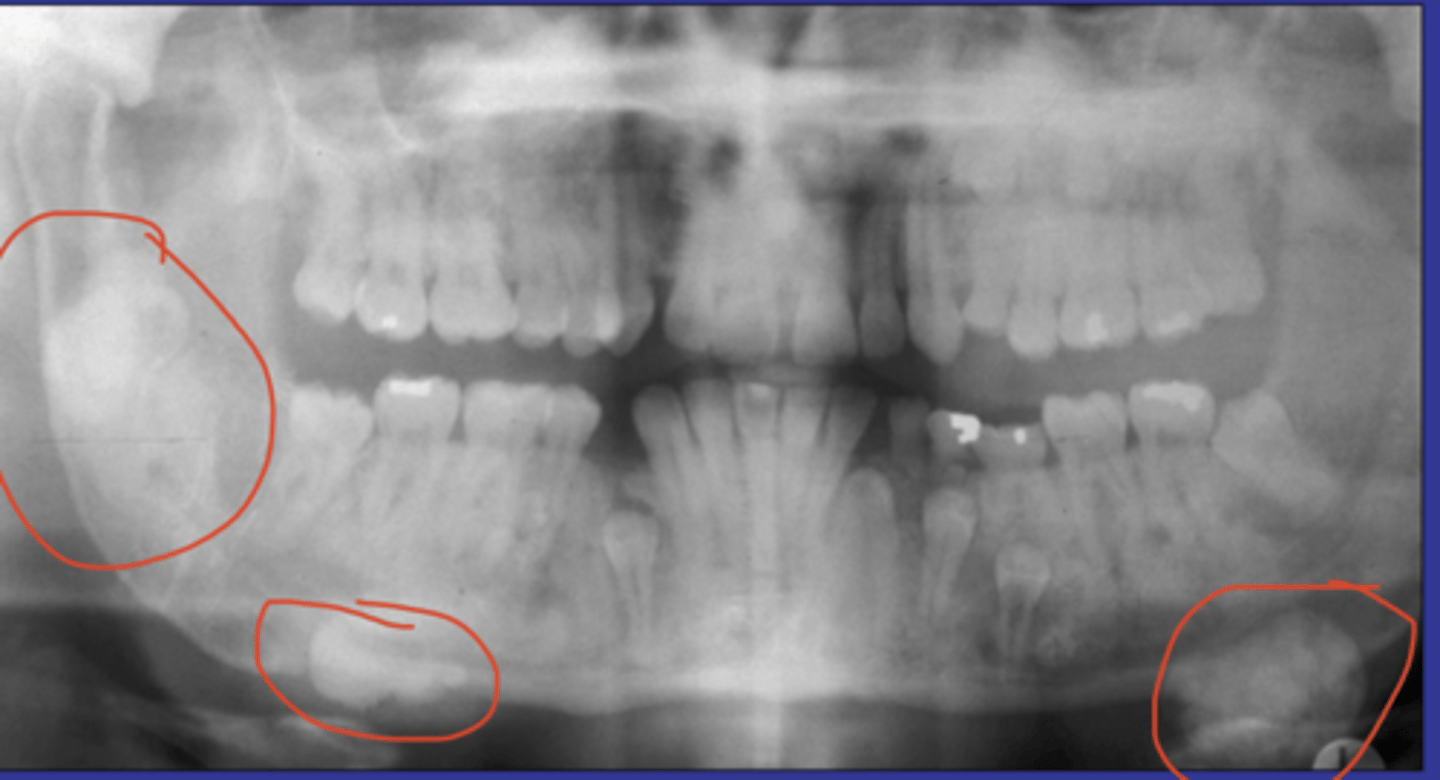

ameloblastoma (+ common location, associations/radiographic appearance, population)

common locations: posterior mandible

clinical features: asymptomatic; unerupted teeth

radiographic: uniocular, multiocular (soap/bubble honeycomb),

appearance: bone expansion, resorbs + displaces teeth

population: young>>middle aged, wide range